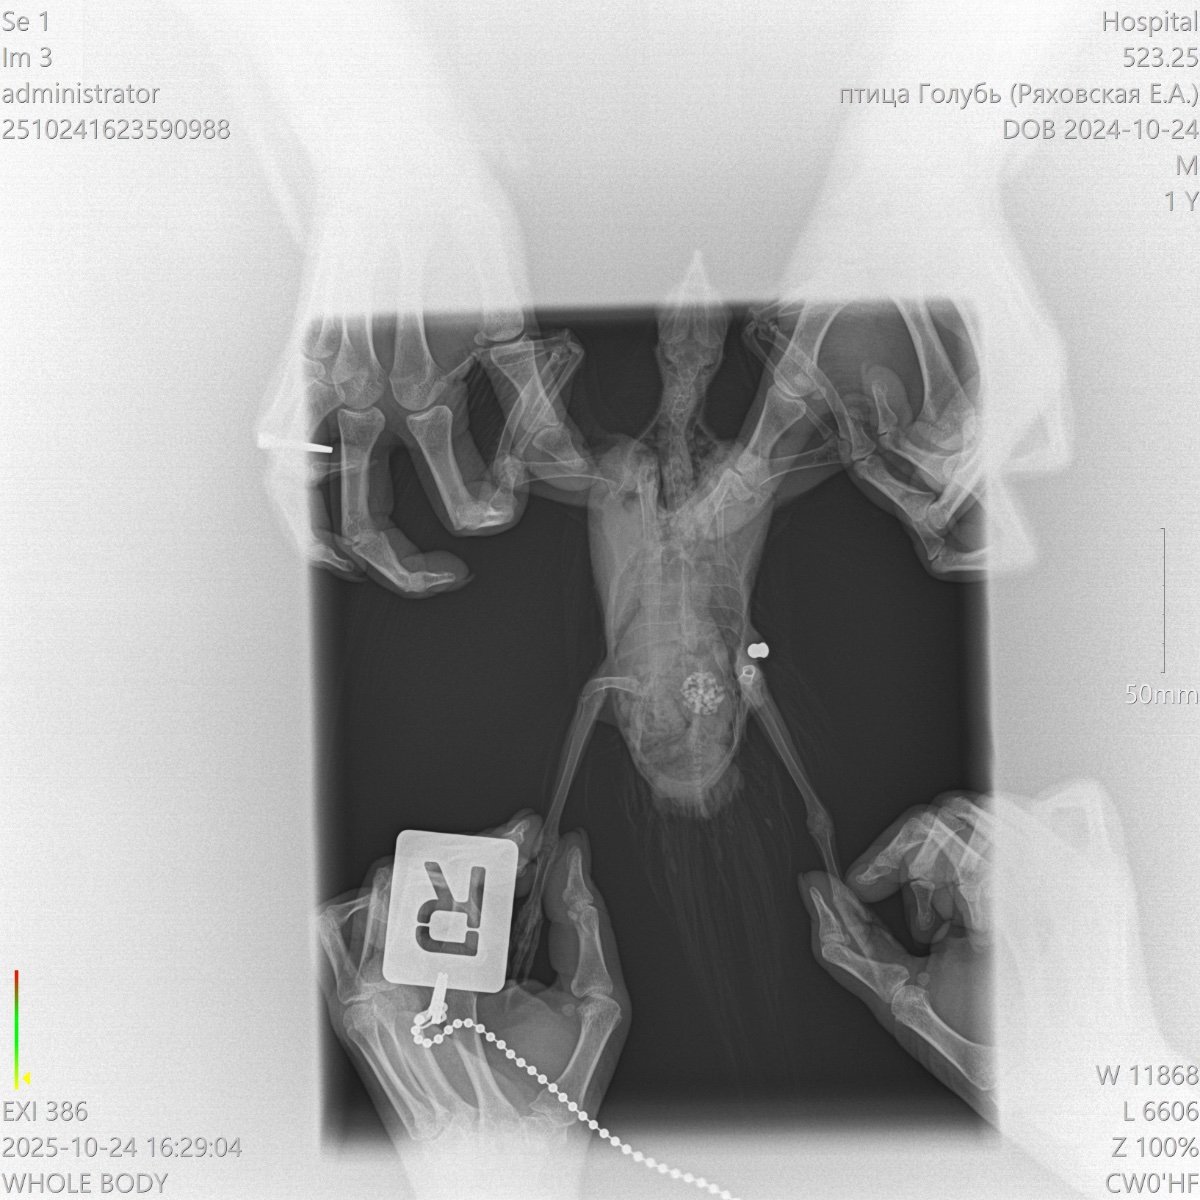

У голубя не функционируют лапки

Добрый день! Подобрали голубя, не встает на лапки, у нас в городе нет орнитолога, ветеринар не может точно сказать что с птицей. Помет зеленого цвета, кушает хорошо, перья блестят, очень активный.

Может ли это быть перелом позвоночника? Если да, то есть ли у птицы шанс встать на лапы?